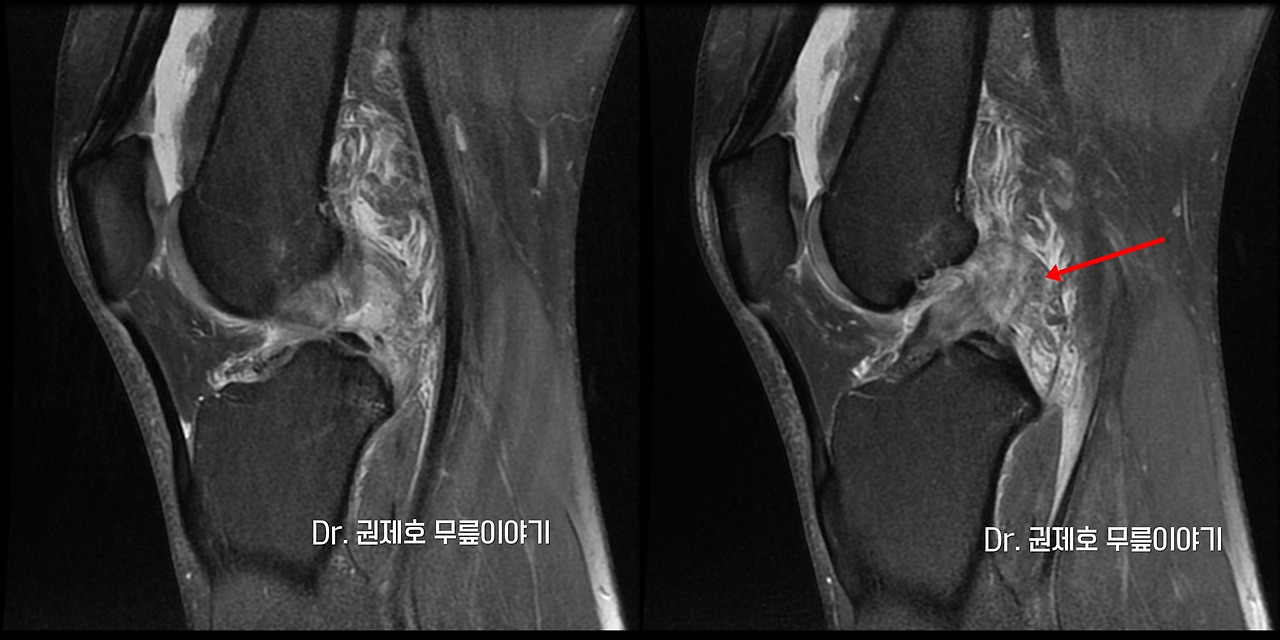

전방십자인대파열 타가건 재건술 (2).jpg 환자분의 MRI

의심되는 부위를 객관적으로 확인하는 방법은 현재는 MRI 밖에 없습니다. 십자인대 파열은 옆에서 보는 MRI 영상으로 진단하게 되며 위의 사진에서 보면, 화살표가 있는 부위가 전방 십자인대가 파열된 모습입니다.